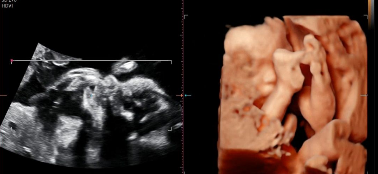

숨이 턱턱 막히는 더위에 주말 내내 방콕~ 어제도 소고기로 철분 보충하고, 낮잠도 필수였지. 저녁 먹은 후엔 운동도 20분 했는데, 피곤했는지 밤에도 금방 잠들었어. 엄마 배가 하루 하루 쑥쑥 나오고 있어. 새로운 옷을 장만해야하는데, 인터넷 쇼핑은 자꾸 실패해서 모두 반품 중이란다. 오늘 외할머니랑 같이 아울렛에 가볼게. 이제 복덩이는 26주차가 되었어! 이번주에는 몸무게가 1kg 가까이 늘어난대~ 복덩아, 네 이름을 뭘로 지을까 아직도 고민 중이란다. 건강하게 자라서 만나자♡♡♡